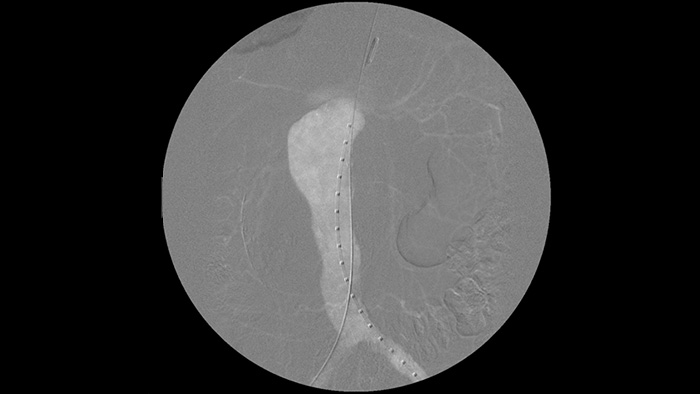

CO2造影剤機能を使用することによって腎不全患者に対する血管手術治療をヨード造影剤を使用せずに安心して血管描出を行うことができます。